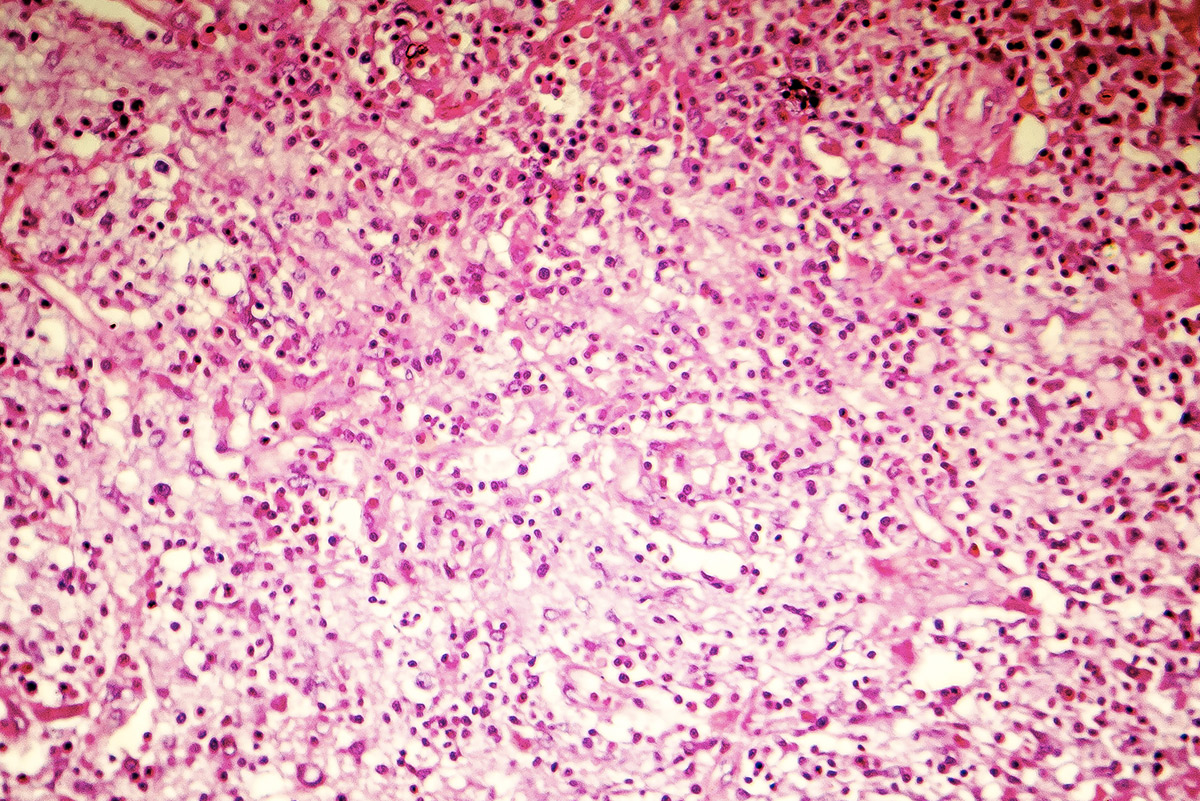

Hauptanwendungsgebiete sind die Medizin und Biologie, wo Eosin Y zum Färben von Zellen, u. a. im Blut (siehe auch eosinophile Granulozyten und Hämatoxylin-Eosin-Färbung) dient. Dabei werden Zellbestandteile wie z. B. das Zytoplasma rötlich angefärbt. Neben Eosin Y kann für manche Anwendungen auch Eosin B eingesetzt werden.